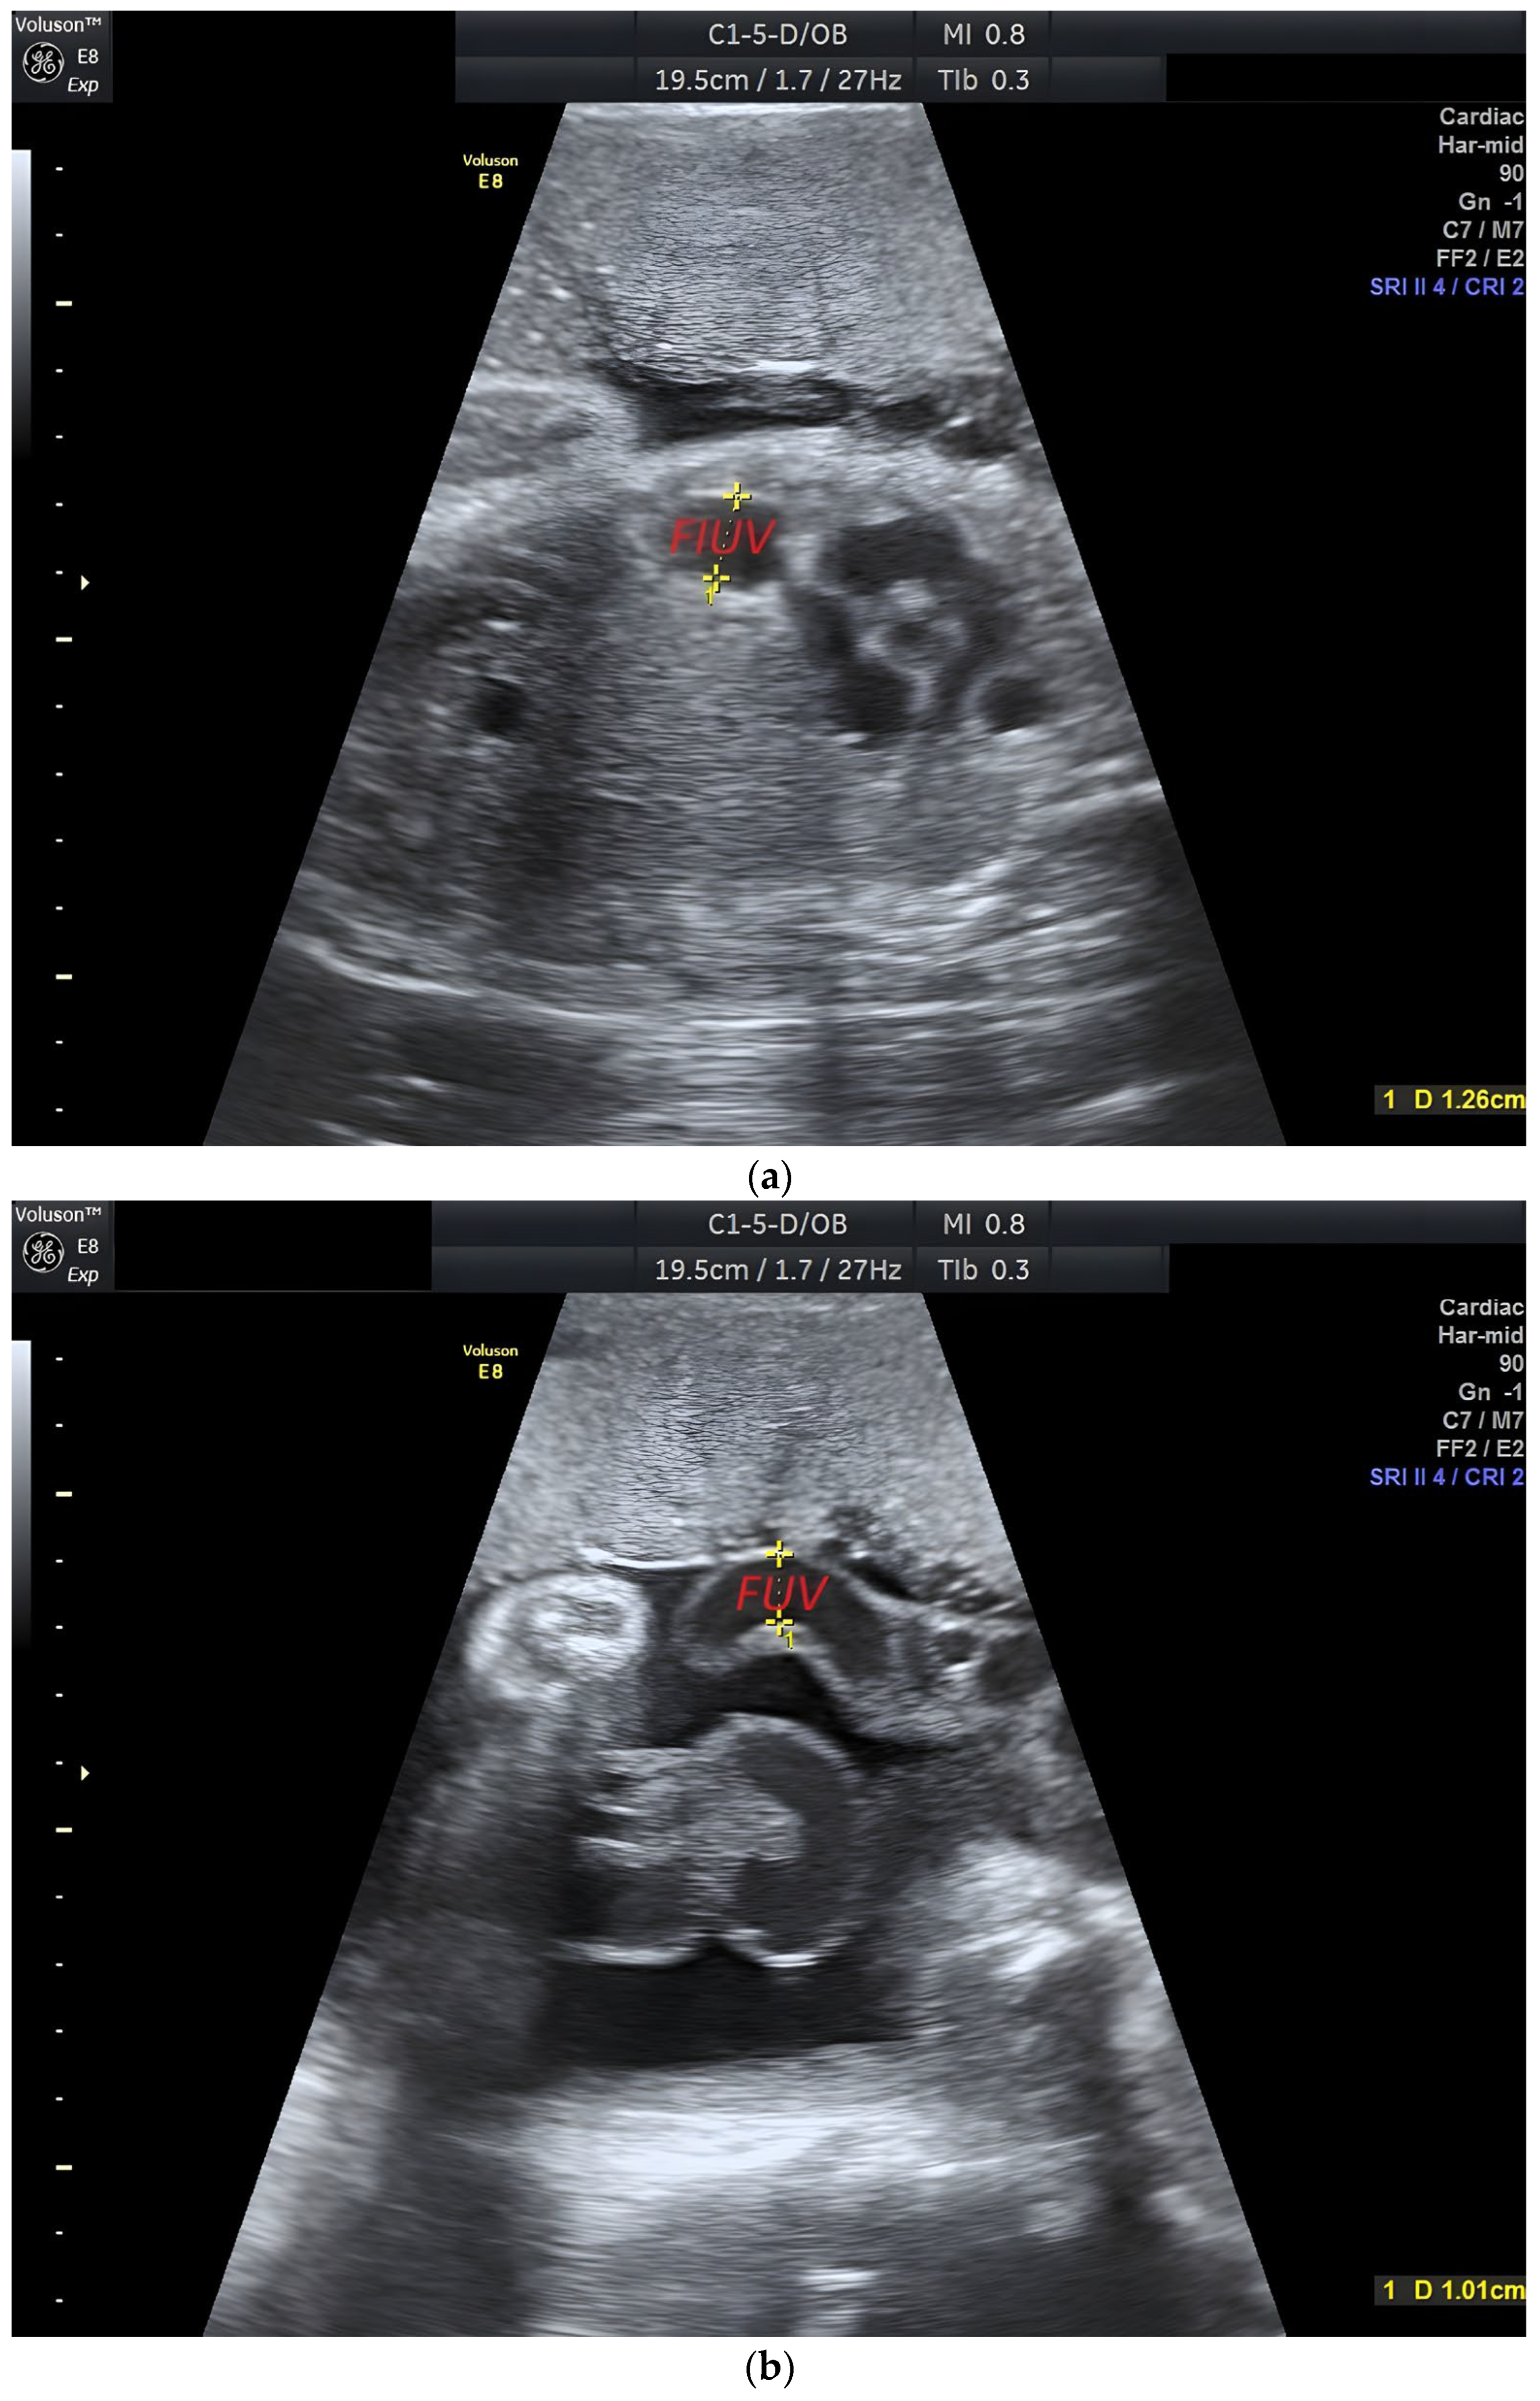

| FIUV | Intra-abdominal umbilical vein |

| FUV | Extra-abdominal umbilical vein |